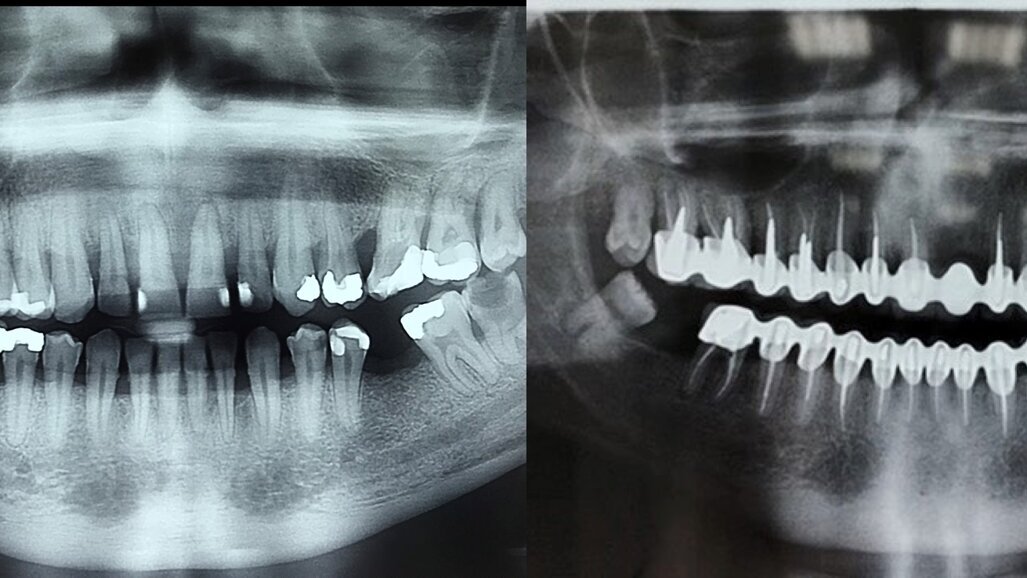

Pacijent starosti 29 godina, s agresivnom formom parodontitisa. Pacijent je u trajanju od 2 godine lečen nehirurškom, a zatim i hirurškom terapijom oboljenja parodoncijuma uz primenu preparata GelCide. Nakon 2 godine, pacijent je protetski rehabilitovan fiksnim protetskim radom.